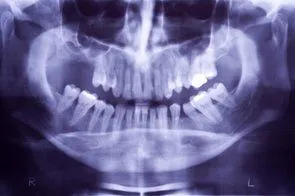

Loss of posterior teeth may result in excessive forces iStock_000002879017XSmall.jpg being placed on your remaining teeth.  Fortunately, the use of dental implants and crowns allow you to replace these missing teeth.  However, the position of the sinus in the upper posterior areas may be too low for proper placement of dental implants.

A simple procedure allows the sinus floor to be repositioned, creating enough space to properly place an implant.  Various grafting materials are used to encourage your bone to grow more quickly into the area, helping to stabilize the dental implant. Replace with your own bone in this area the grafting material as it grows into the area.

Under certain conditions, an even simpler procedure can be utilized.  When possible, the bone remaining under the sinus floor is gently “pushed up”, thus lifting the floor of the “dropped” sinus.  Bone replacement materials are then placed beneath this lifted bone.  Once again the bone materials are replaced as your body grow new bone into this area.

Sinus augmentation procedures are highly predictable, with studies reporting over 95% success.  Following sufficient healing of a sinus augmentation (6-10 months), implants are placed in a predictable and successful manner.  It is important to realize that if the sinus augmentation procedure does not result in enough bone for implant placement, additional bone may be regenerated through a second sinus augmentation procedure at the time of implant placement.